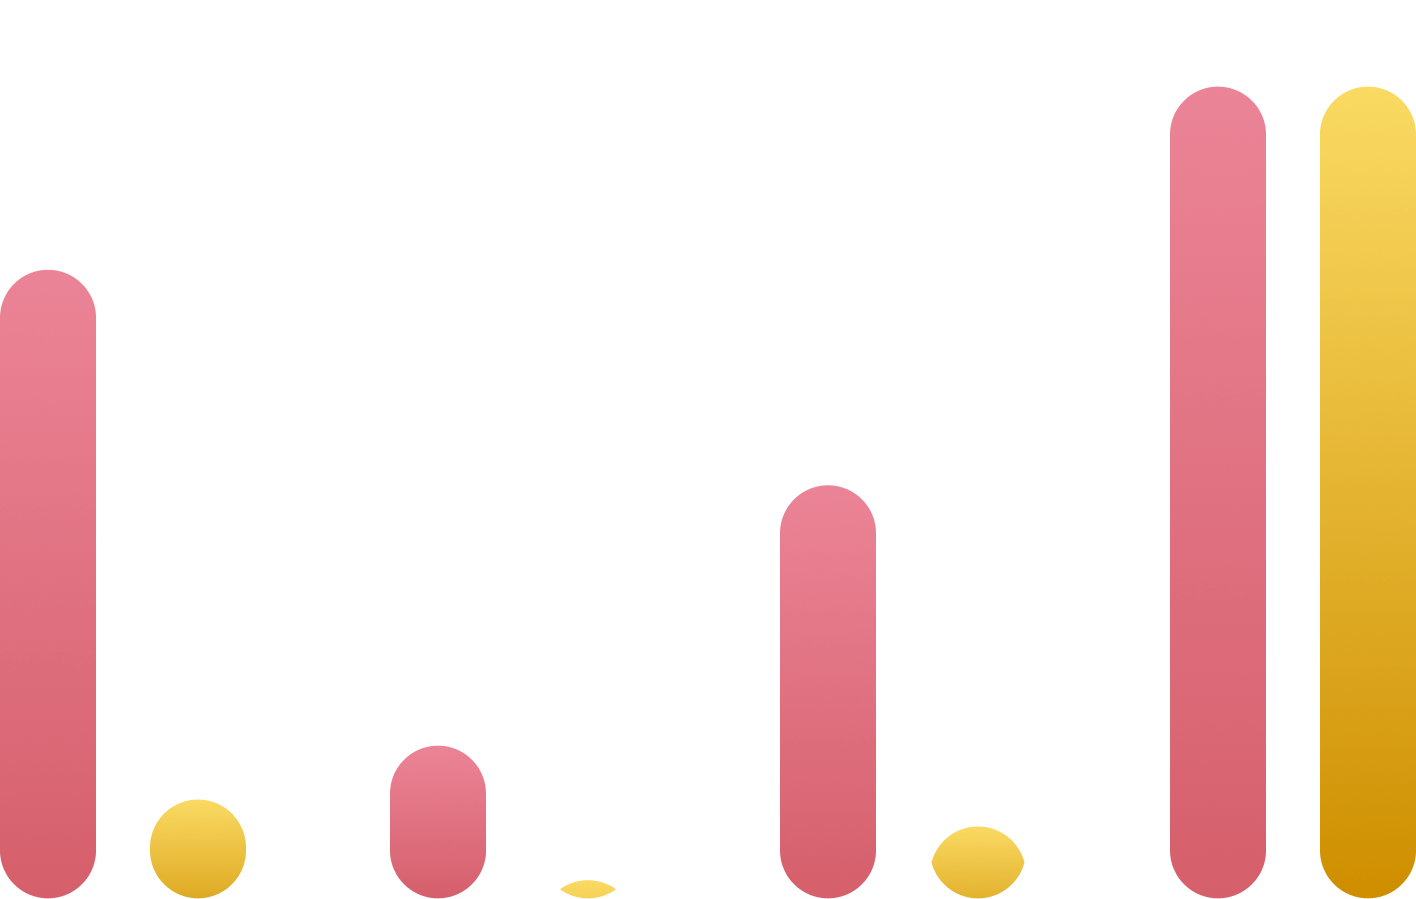

Фурамаг® — эффективное средство для лечения инфекций мочевыводящих путей

- Пушкарь Д. Ю., Берников А. Н., Раснер П. И., Бормотин А. В., Дьяков В. В., Шведов А. М. Фуразидин (Фурамаг®) в лечении острого и рецидивирующего цистита у женщин. Вестник урологии. 2024;12(6): 83-88. DOI: 10.21886/2308-6424-2024-12-6-83-88.